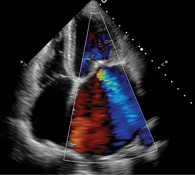

Рис. 1. Эхокардиография: выраженная недостаточность митрального клапана на момент поступления

По данным ЭхоКГ: отмечается фиброз створок митрального клапана, отрыв хорд задней створки митрального клапана с формированием регургитации 3-й степени (рис. 1), фиброз створок легочного клапана, пиковое давление в стволе легочной артерии – 50 мм рт. ст., фиброз створок аортального и трикуспидального клапанов без нарушения гемодинамики, отмечается дилатация полости левого предсердия – до 97 мл, объемы левого желудочка (ЛЖ) – в пределах нормы, локальная сократимость и глобальная функция ЛЖ – не нарушены, фракция выброса – 66%, диастолическая дисфункция ЛЖ 2-го типа, объемы правых камер сердца – не увеличены. По результатам селективной коронарной ангиографии, гемодинамически значимого поражения коронарных артерий не выявлено. В качестве дообследования выполнена магнитно-резонансная томография сердца с внутривенным контрастированием, по результатам которой выявлен протяженный фиброз миокарда ЛЖ в базальных, средних и верхушечных отделах – суммарно 6,8% (рис. 2).